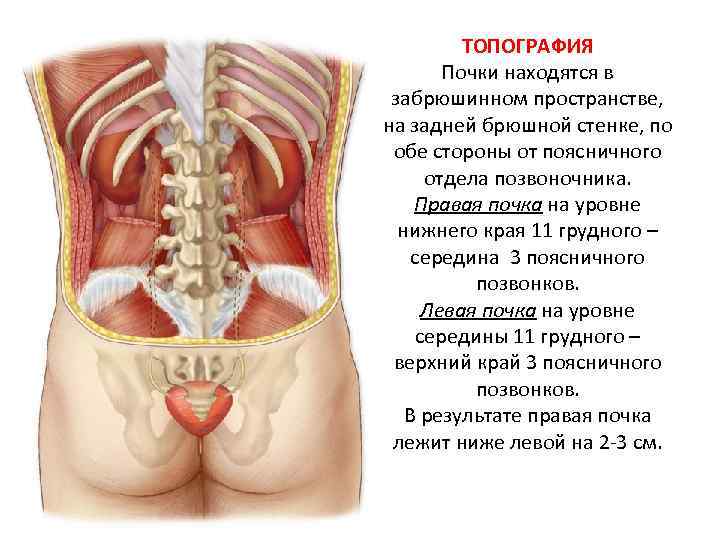

ТОПОГРАФИЯ Почки находятся в забрюшинном пространстве, на задней брюшной стенке, по обе стороны от поясничного отдела позвоночника. Правая почка на уровне нижнего края 11 грудного – середина 3 поясничного позвонков. Левая почка на уровне середины 11 грудного – верхний край 3 поясничного позвонков. В результате правая почка лежит ниже левой на 2 -3 см.

ТОПОГРАФИЯ Почки находятся в забрюшинном пространстве, на задней брюшной стенке, по обе стороны от поясничного отдела позвоночника. Правая почка на уровне нижнего края 11 грудного – середина 3 поясничного позвонков. Левая почка на уровне середины 11 грудного – верхний край 3 поясничного позвонков. В результате правая почка лежит ниже левой на 2 -3 см.